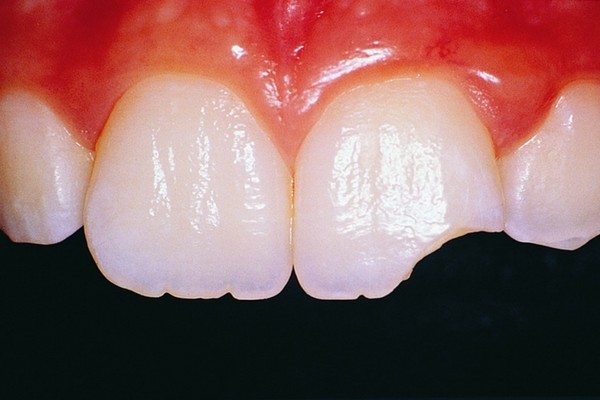

A bruised tooth is often caused by an injury to the tooth. Similar to a bruise on your skin, a bruised tooth is a reaction to excess pressure or force. While your tooth won’t turn black and blue like your skin, it can become discolored and turn a gray tint.

A bruised tooth is painful and may ache because the soft tissue and ligaments around your tooth essentially absorb the impact of the trauma or injury. Just like a bruise on your skin, the capillaries around the injured tooth burst. The capillaries then travel to the opening of the tip of the root, which gives the tooth a pinkish discoloration.

The pinkish discoloration may turn gray, which can be permanent. A gray tooth may mean that the pulp inside your tooth is impacted, resulting in a higher risk of infection or decay. This can result in the need for a root canal Brentwood. If your tooth does not turn from pink to gray, you may be in the clear. However, you should see the best dentist Brentwood has, as they will want to monitor your tooth and help you in identifying a bruised tooth.